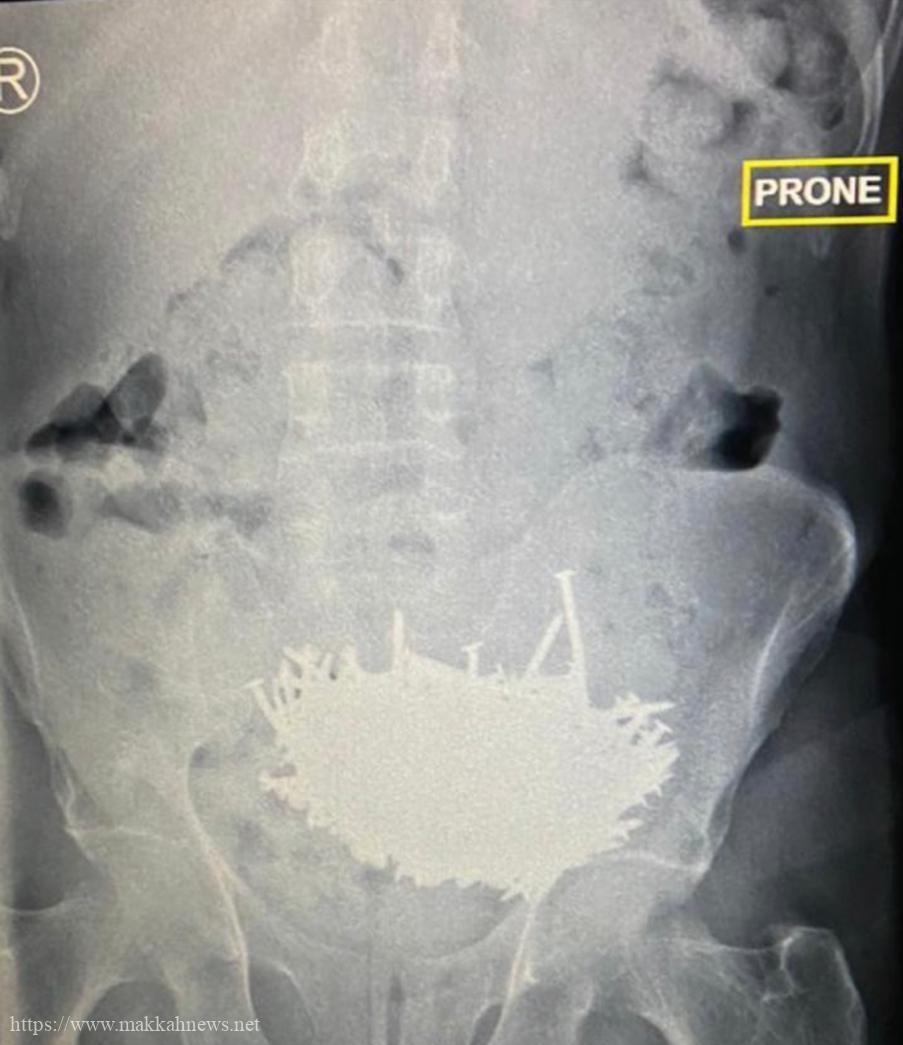

تدخل طبي ناجح ينقذ حياة مريض نفسي بمستشفى ” شرق جدة “

جدة : أسهم بفضل الله فريق طبي في مستشفى شرق جدة مكون من إستشاريين وأخصائيين من قسم الجراحة والتخدير في…